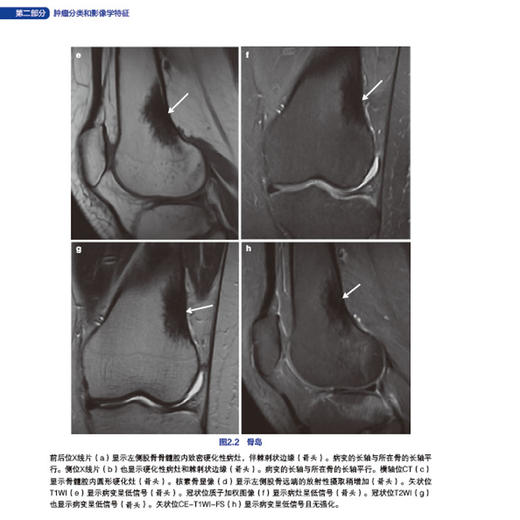

22 骨岛016